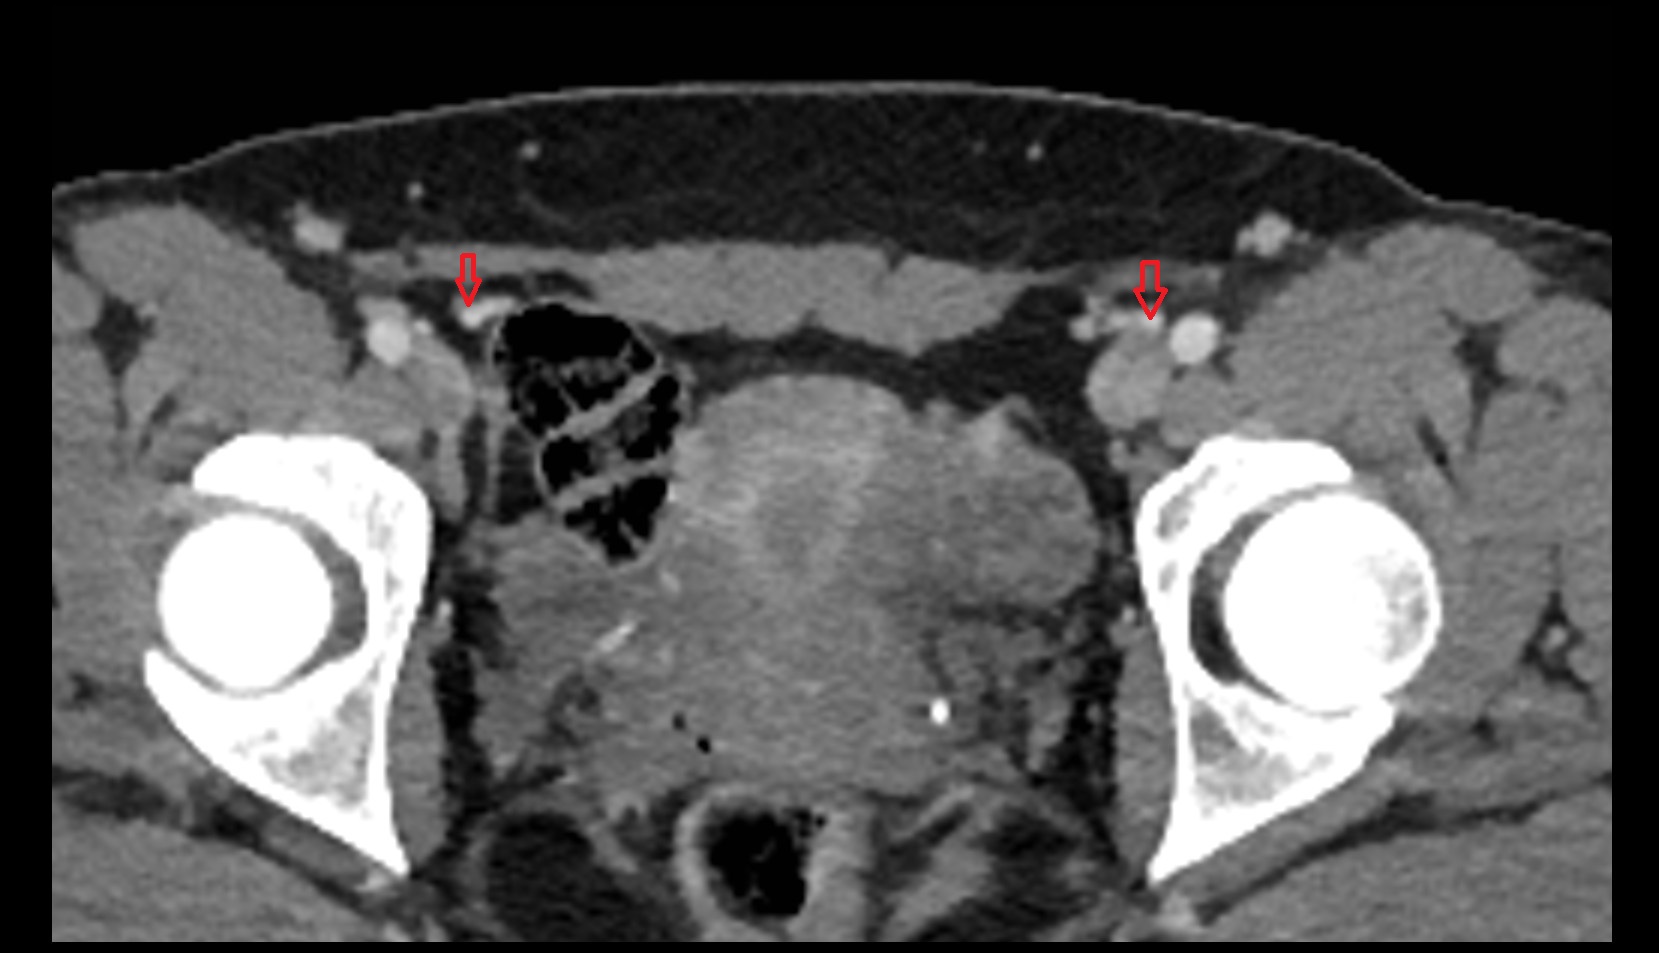

- Sciatic nerve

- Obturator nerve

- Inguinal lymph nodes

- External iliac lymph nodes

- Obturator lymph nodes